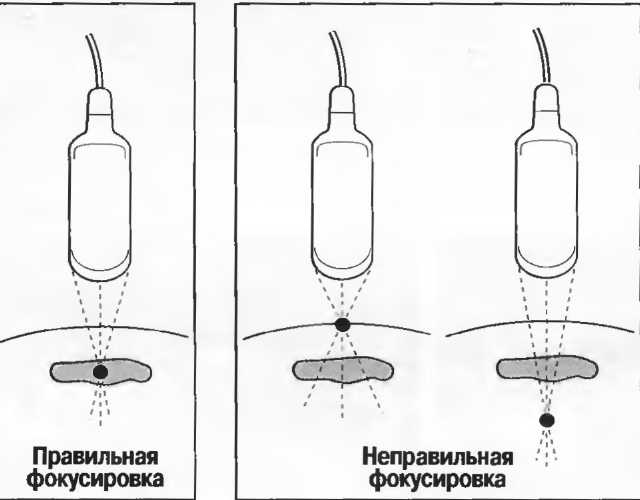

Фокусировка может осуществляться линзами, зеркалами или электронным путем в многоэлементных датчиках. Как узко направленный пучок света более четко показывает объект, чем более рассеянный, несфокусированный поток, так и фокусированный ультразвук дает более тонкий срез ткани, в результате чего изображение получается более детальным. Для получения наилучшего результата необходима фокусировка на той глубине, которая наилучшим способом соответствует поставленной клинической задаче. Для аппаратов общего назначения это означает использование специальных датчиков для различных целей и, при необходимости, использование программы фокусировки аппарата (рис. 3).

Рис.3. Центр изображения в фокусе, в то время как периферия — нет.

Различные варианты фокусировки

Многие трансдьюсеры имеют фиксированный фокус. Многоэлементные трансдьюсеры, например линейные или конвексные, а также аннулярные секторные имеют электронно задаваемое фокусное расстояние, устанавливаемое на требуемую глубину. Тем не менее многие трансдьюсеры имеют фиксированное фокусное расстояние: только аннулярные секторные датчики имеют электронную фокусировку во всех плоскостях. Регулирование фокусировки обеспечивает узкий акустический поток и более тонкую плоскость среза: это дает более высокую разрешающую способность и более четкое изображение с большей информацией.

Рис. 12. Фокусировка правильна слева, так как визуализируются детали желточного мешка. Справа детали не видны, так как фокусное расстояние значительно больше.